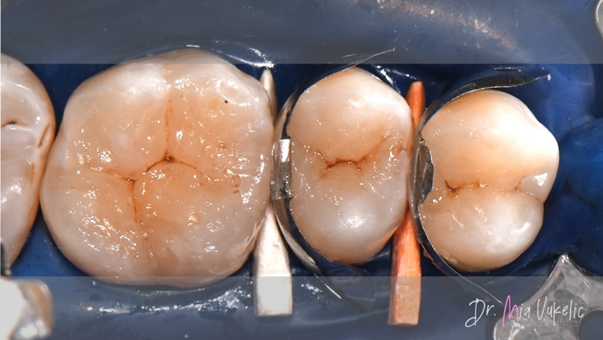

De patiënt bezocht de kliniek voor een jaarlijkse controle. Uit het klinisch en röntgenonderzoek bleek een secundaire cariëslaesie op het occlusale vlak van gebitselement 26 en twee cariëslaesies op de distale vlakken van gebitselement 24 en 25. De patiënt meldde geen specifieke symptomen. De voorgeschreven behandeling bestaat uit het aanbrengen van een klasse I-restauratie op gebitselement 26 en klasse II-restauraties op gebitselement 24 en 25.

Na goede isolatie met een rubberdam en het plaatsen van wiggen werd de caviteit geprepareerd met een cilindrische boor. Na het verwijderen van de restauratie werd gedemineraliseerd dentine weggehaald met behulp van een stalen boor. Tot slot werden de convergente wanden omgevormd in divergente wanden en werd het inwendige oppervlak van de caviteit gepolijst met diamantpolijstboren.